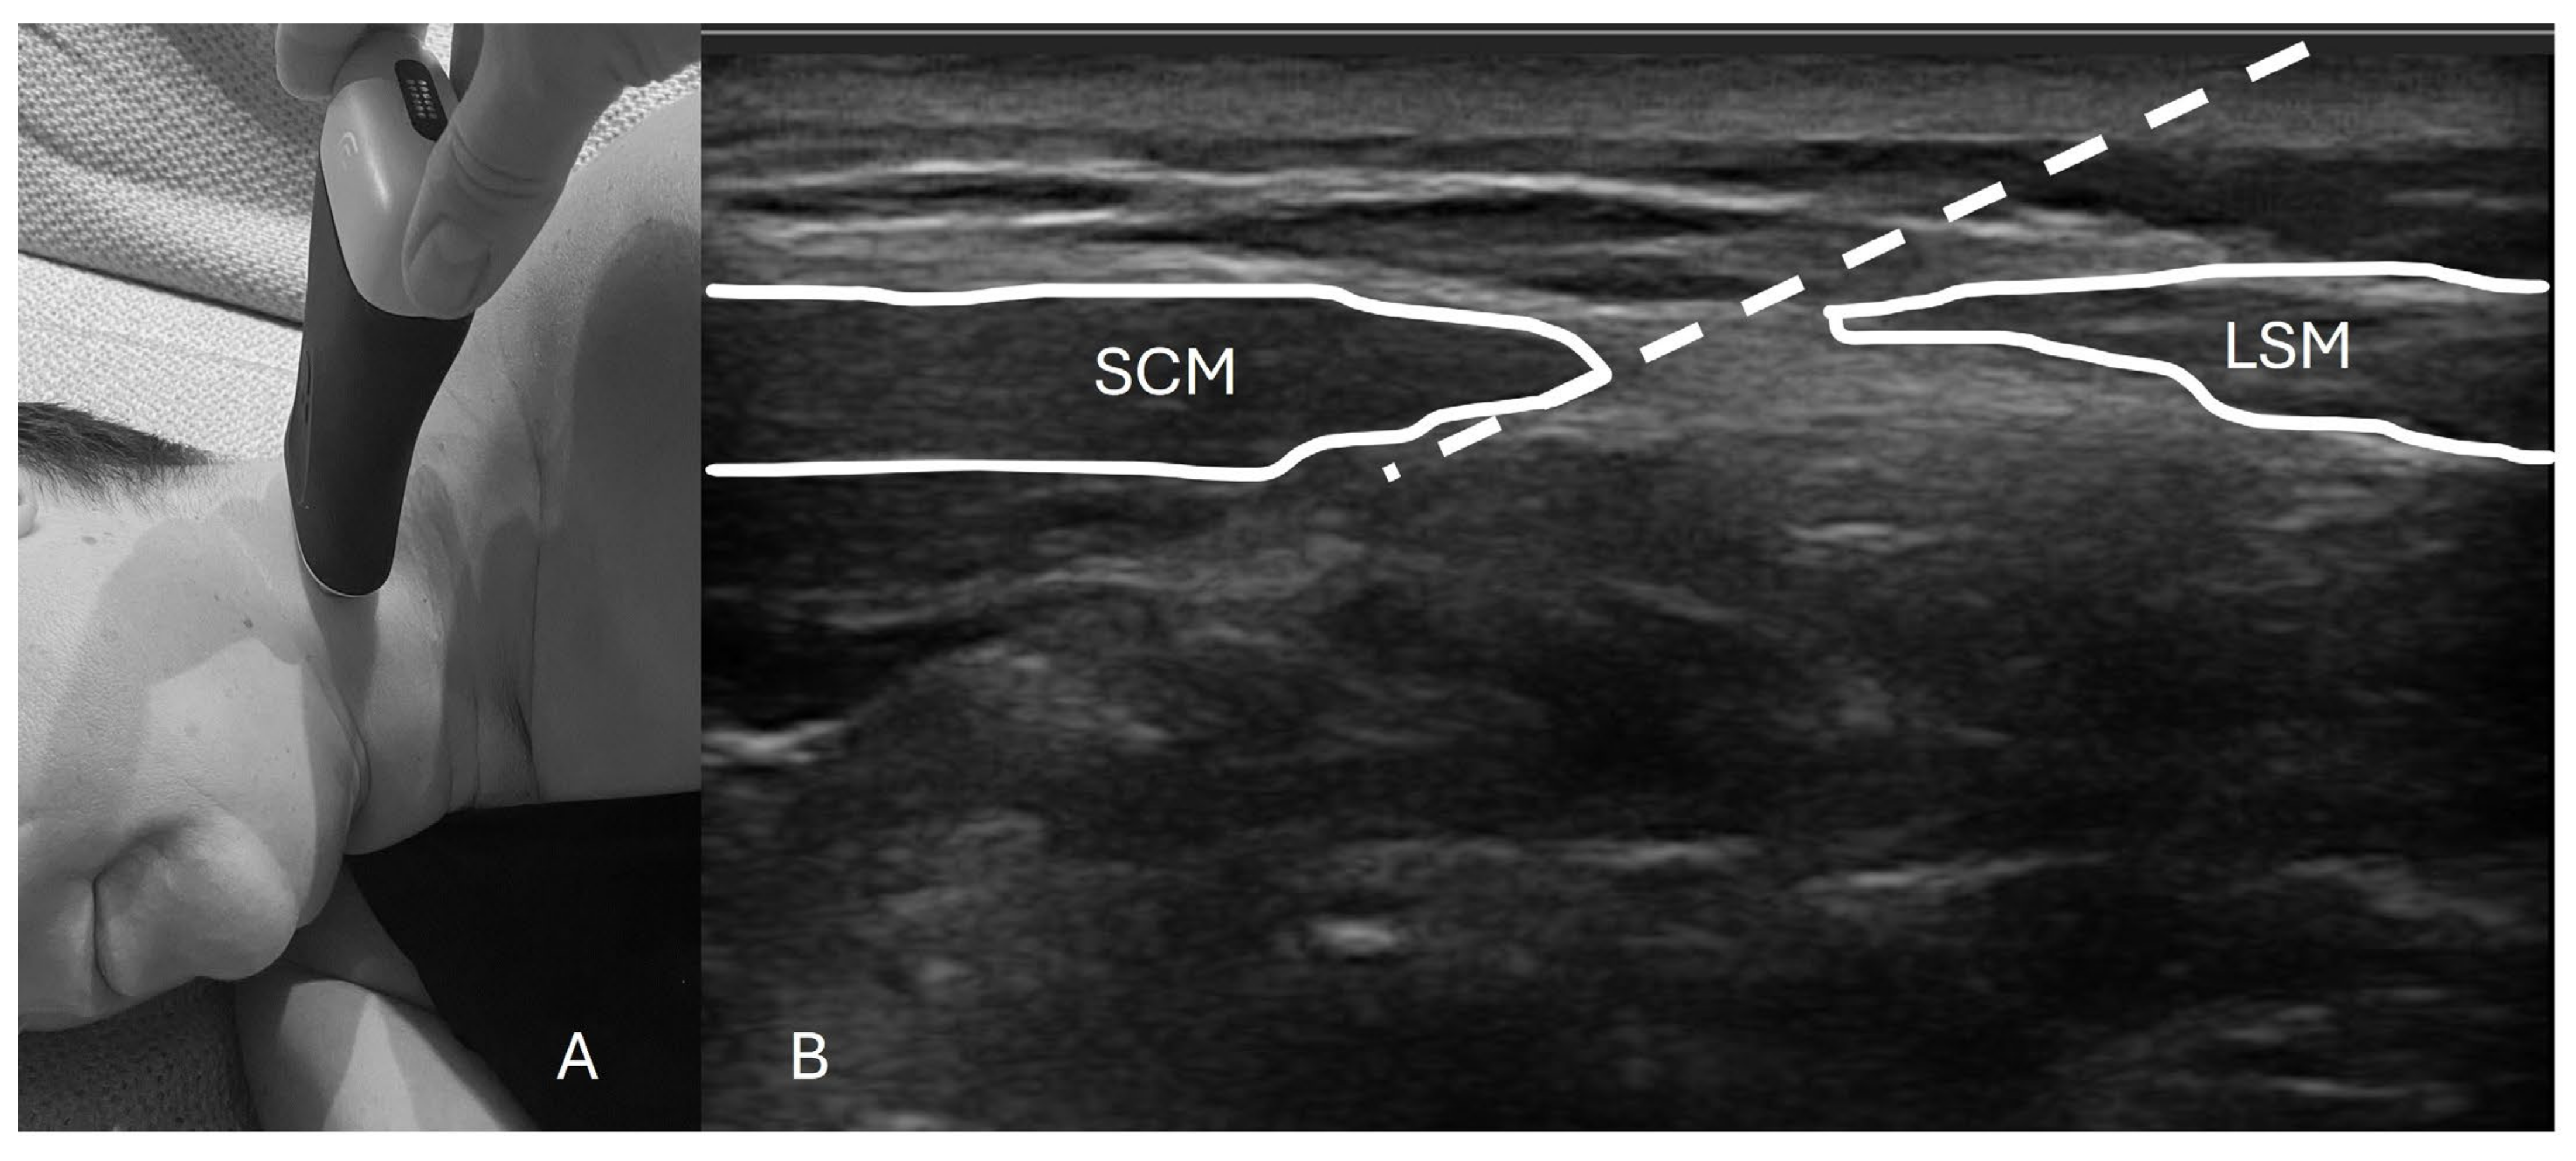

2.2.2. Superficial Cervical Plexus Block Technique

3.3. Technical Description